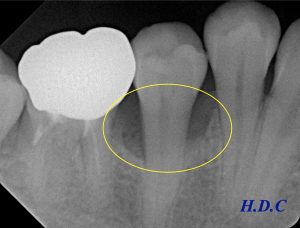

歯周ポケット検査を行ったところ、右下の小臼歯に8mmの深い歯周ポケットを認め、レントゲン上でも骨が溶けていることが確認できます(左下レントゲン黄色い枠の中、歯の根の周りの黒くなっている場所)。

左下のレントゲンが初診時、右下のレントゲンがエムドゲイン治療後2年経過時です。

歯周病で溶けてしまった骨の再生が確認できます(黄色い枠の中)。外科治療前に8mmあった歯周ポケットも、2~3mmに改善しました。患者さん自身の良好なプラークコントロールにも助けられ、順調な経過を辿っています。